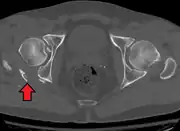

Posterior wallThis is the most common variety of acetabular fracture. It typically occurs due to dashboard injury; when a person travelling in a vehicle involved in a head-on collision, the force applied over the flexed knee travels along the femur bone to the head of the femur, breaking the posterior wall of the acetabulum. The head of the femur is dislocated outside the joint. T shapeWhen a transverse fracture also had a vertical fracture line, it is called a T shape fracture. Here the innominate bone is broken in such a way that all three parts of it, the ilium, the ischium and the pubis are separated from one another. This is a three part fracture. Though both columns are broken, the weight bearing dome is still attached to the main part of the ilium and hence it is not a true fracture of both columns.

• Posterior wall fracture: Iliac oblique and obturator oblique views